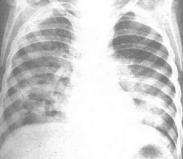

老年肺炎

• 老年肺炎

628健康網為您分享有關老年肺炎的癥狀,老年肺炎的治療方法,老年肺炎的預防知識,老年肺炎的癥狀圖片,老年肺炎吃什么藥,老...